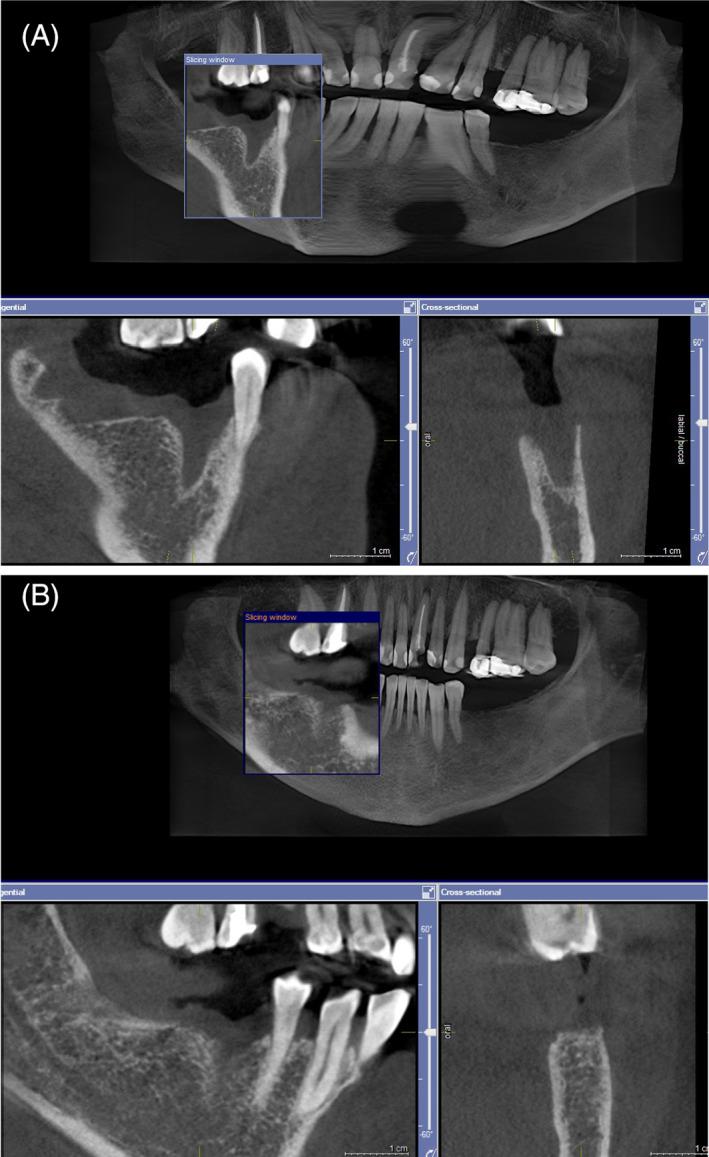

This study aimed to evaluate a comprehensive laser post-extraction protocol by comparing resulting alveolar bone regeneration with that obtained after standard extraction procedure.

About 53 simple extractions were randomized to either laser or control group. In the laser group, erbium (Er:YAG; 2940 nm) and neodymium (Nd:YAG; 1064 nm) lasers were used for degranulation, disinfection, de-epithelialization of the surrounding gingiva, clot stabilization, and photobiomodulation. The primary outcome measure was change in bone density in the extraction area between day 1 and 4 months after extraction. Patients were monitored for potential side effects.

Increase in bone density at the follow-up CBCT was significantly higher in laser than in control group (p < 0.001). No post-operative pain, bleeding, or swelling was present in the laser group. In the control group, one patient had bleeding 3-5 days after extraction, two patients had swelling and three patients reported post-operative pain rated 3-5 on a 0-10 pain scale up to 3 days after extraction.

材料与方法

大约 53 例简单拔牙被随机分为激光组或对照组。在激光组中,使用铒(Er:YAG;2940nm)和钕(Nd:YAG;1064nm)激光进行脱颗粒、消毒、周围牙龈去上皮化、血凝块稳定和光生物调节。主要观察指标为拔牙后 1 天至 4 个月拔牙区骨密度的变化。监测患者的潜在不良反应。

结果

激光组在随访 CBCT 中骨密度的增加明显高于对照组(p<0.001)。激光组无术后疼痛、出血或肿胀。对照组中,1 例患者在拔牙后 3-5 天出血,2 例患者肿胀,3 例患者在拔牙后 3 天内报告术后疼痛评分 3-5(0-10 疼痛评分)。